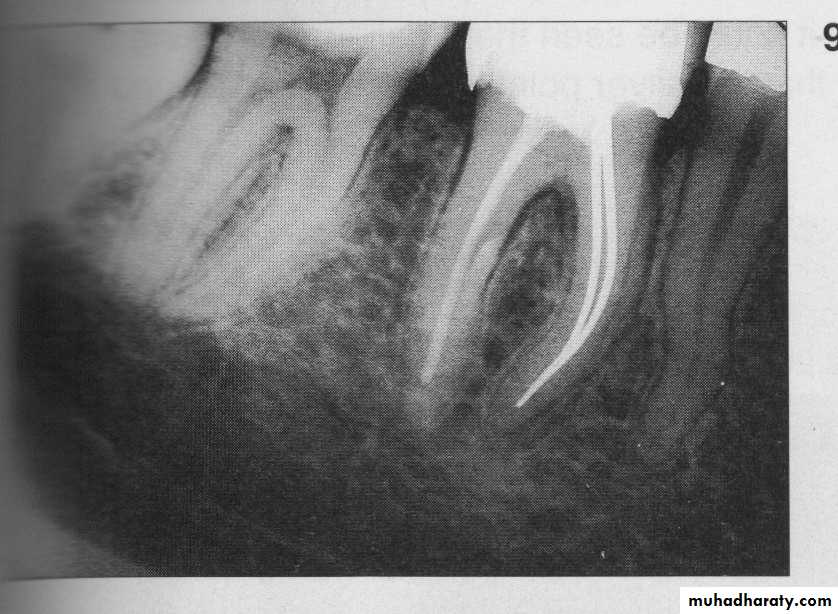

Verify the master cone position with a radiograph to ensure the optimum fitness.

take aradiograph to check the obturation mass.